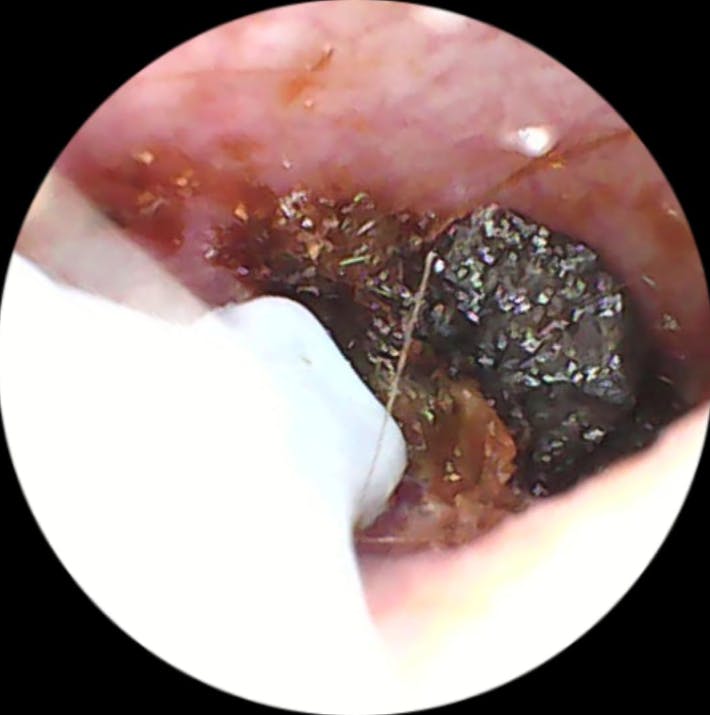

Mit diesel Gerät kann ich selbst in regelmäßigen Abständen das Ohr vom gröbsten Ohrenschmalz befreien. Mit diesem Gerät tut es überhaupt nicht weh, die Aufnahmen der Kamera sind sehr gut. Mit etwas Geduld, Übung und Vorsicht kann man das Ohr wirklich sehr gut reinigen, ohne es zu verletzen. Ich kann das Produkt ohne Vorbehalte weiterempfehlen und würde es wieder kaufen.

Dache das meine Ohren eigentlich sauber wären, aber naja, was soll ich sagen 😂

Meine Ohren waren ziemlich dreckig, hab damit aber fast alles rausbekommen. Bin zufrieden

Meine Ohren waren soooo verstopft, das hätte ich mir nie gedacht. Hab aber zum Glück alles rausbekommen, das Gefühl ist auch richtig angenehm gewesen, fast schon satisfying